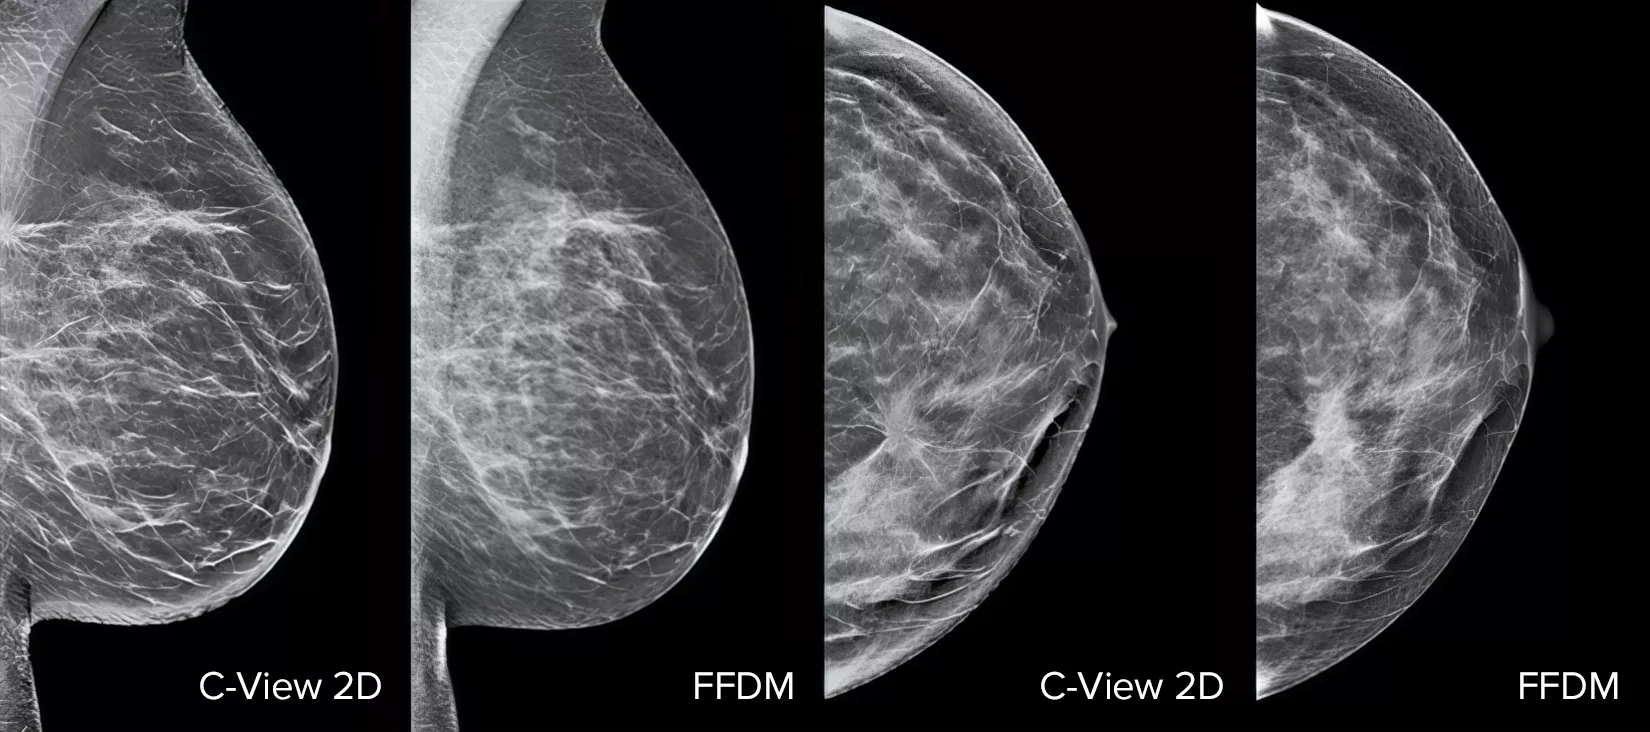

Röntgenbilder av bröst

Strukturella distorsioner, expansiva lesioner och ljusa fläckar som vanligtvis förekommer i mikroförkalkningar är synligare på en C-View 2D-bild än på traditionella FFDM 2D-bilder eller tomosyntessnitt.4, 6–9

C-View 2D-bilder är kliniskt bevisade3, 5 och FDA-godkända för att diagnostiskt ersätta FFDM-bilderna i en screeningundersökning med tomosyntes. Bilderna är även en navigeringshjälp vid granskning av tomosyntessnitt. Publicerade studier påvisar att 3D-mammografiundersökning vid låg dos hittar invasiv cancer tidigare, samtidigt som den även minskar frekvensen av falskt positiva återkallade, jämfört med enbart 2D.4, 5, 7